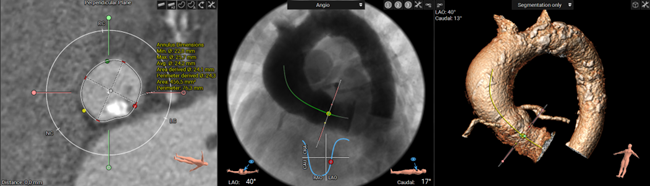

Another useful feature is the automatic annular plane segmentation with the cusp detection, which is a real time saver. This along with the simulated angio view and the automatic cusp overlap view gives optimal c-arm angulation which reduces procedure time and saves radiation.

3mensio has established a simplified workflow in which the aortic annulus plane is defined. Coronary heights can be easily measured which is important because coronary obstruction, while rare, can have grave consequences. Also, after choosing the appropriate device size, a virtual valve can be visualized which enables the measurement of the valve to coronary distance (VTC).

Based on the simulated angio view, the coplanar view as well as a cusp overlap view can be generated. These preplanned C-arm angulations are used during the procedure, saving time and radiation."